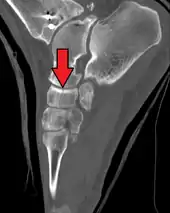

The human navicular is not a commonly broken bone but it breaks due to two reasons. The first mechanism is a stress fracture which happens commonly in athletes [7] and the other mechanism is a high energy trauma.

The navicular bone is a keystone of the foot: it is part of the coxa pedis and articulates with the talus, first, second and third cuneiform, cuboid and calcaneus. It plays an important role in the biomechanics of the foot, helping in inversion, eversion, and motion; it is a structural link between midfoot and forefoot and it is part of the longitudinal and transverse arch of the foot.